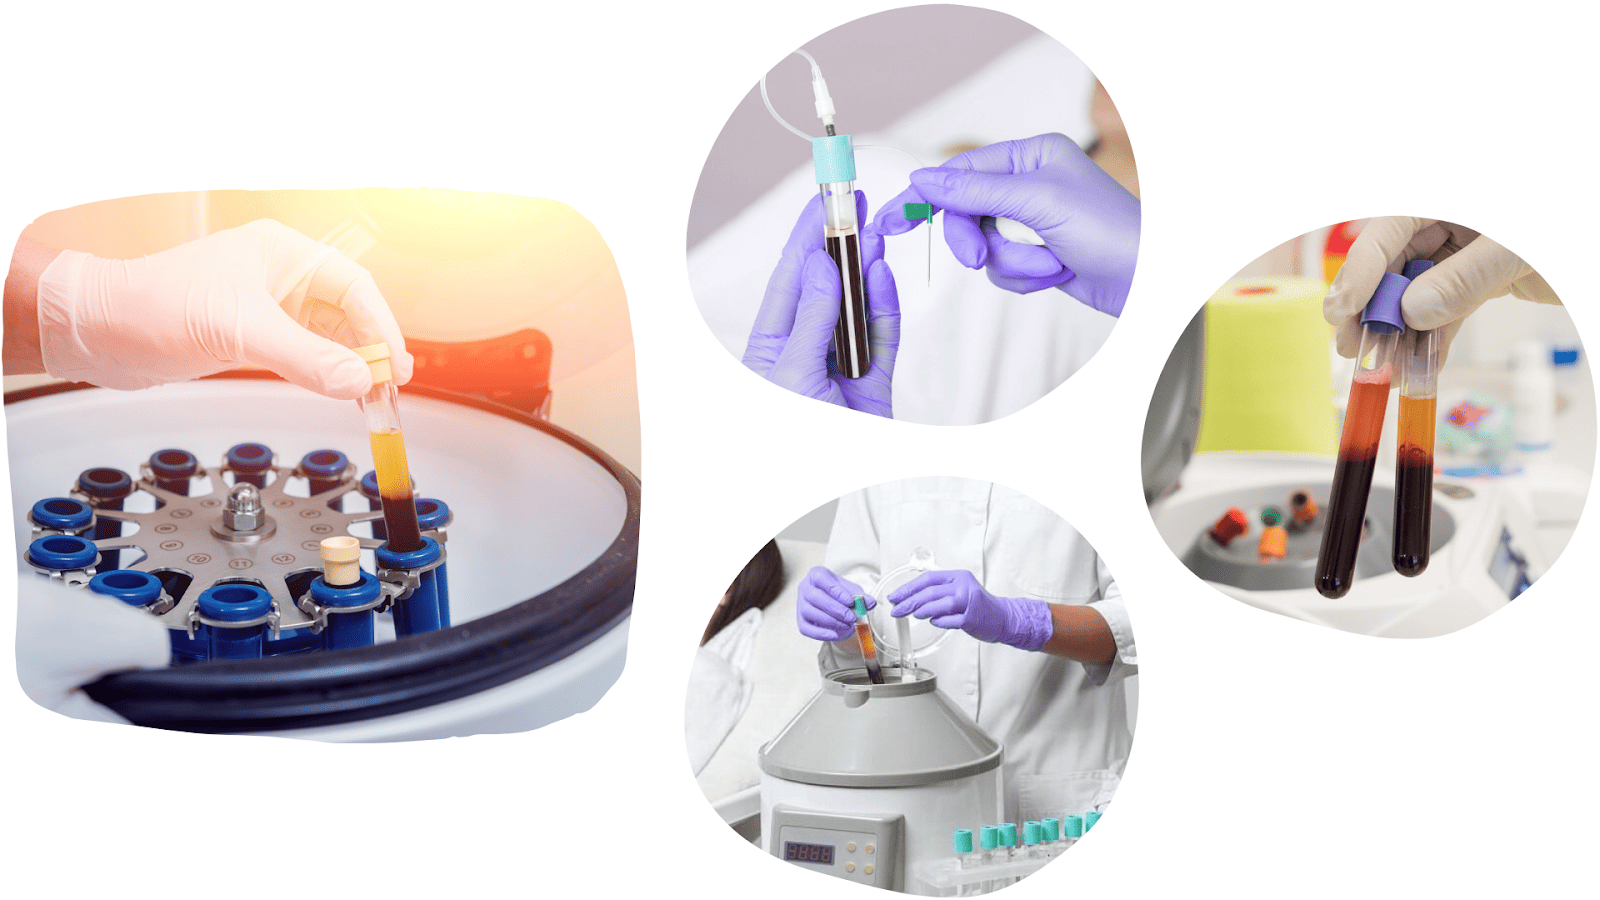

FACIAL REJUVENATION WITH PLATELET-RICH PLASMA

Facial rejuvenation with platelet-rich plasma harnesses the body’s natural power for skin regeneration and rejuvenation.

The procedure is carried out by extracting a small amount of the patient’s blood which, after processing in a high-speed centrifuge, yields platelet-rich plasma that is then applied to the skin using fine microneedles.

It is a completely natural, safe, and personalised method.

Platelets release numerous growth factors that stimulate tissue renewal, the formation of fibroblasts, collagen, and hyaluronic acid.

The result is renewed volume, reduced wrinkles, improved skin elasticity, and a more even complexion. The skin becomes hydrated, fresh, and radiant, with wrinkles becoming less pronounced and shallower.

The advantage of the treatment is that it contains no synthetic substances, there are no side effects, allergic, or immunological reactions.

The procedure is simple, painless, and completely safe, and we use it to treat the face, neck, and décolletage.

Facial rejuvenation with platelet-rich plasma is the best and most natural anti-ageing aesthetic facial treatment you can give yourself.